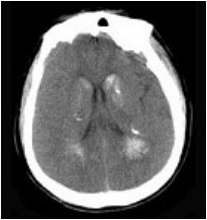

[单选题]男,52岁,无明显不适,CT检查,最可能的诊断为()A.脑血管畸形B.结节性硬化C.甲状旁腺功能低下D.脑颜面血管瘤病E.转移瘤